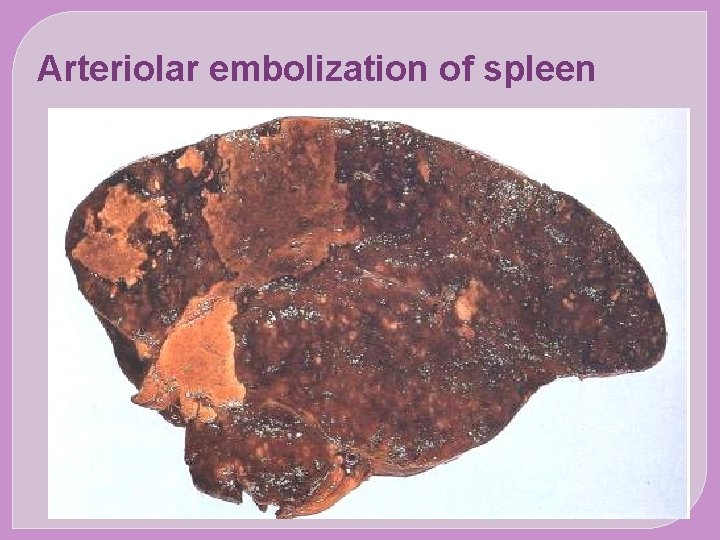

�The major sites for arteriolar embolization are �the lower extremities (75%) and �the brain (10%), �with the intestines, kidneys, and spleen affected to a lesser extent. �The consequences of embolization in a tissue depend on vulnerability to ischemia, caliber of the occluded vessel, and the collateral blood supply; �in general, arterial embolization causes infarction of the affected tissues.

SYSTEMIC EMBOLISM The origin of emboli: Most arise from intracardiac mural thrombi or from ulcerated atherosclerotic plaques The sequel: Arteriolar embolization (e. g. the brain, kidneys , spleen and intesrines)

Arteriolar embolization of spleen